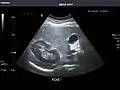

Abdominal ultrasound can be used to diagnose abnormalities in various internal organs, such as the kidneys,[1] liver, gallbladder, pancreas, spleen and abdominal aorta. If Doppler ultrasonography is added, the blood flow inside blood vessels can be evaluated as well (for example, to look for renal artery stenosis). It is commonly used to examine the uterus and fetus during pregnancy; this is called obstetric ultrasonography.[2][3]

Ultrasound scan of a kidney (right side)